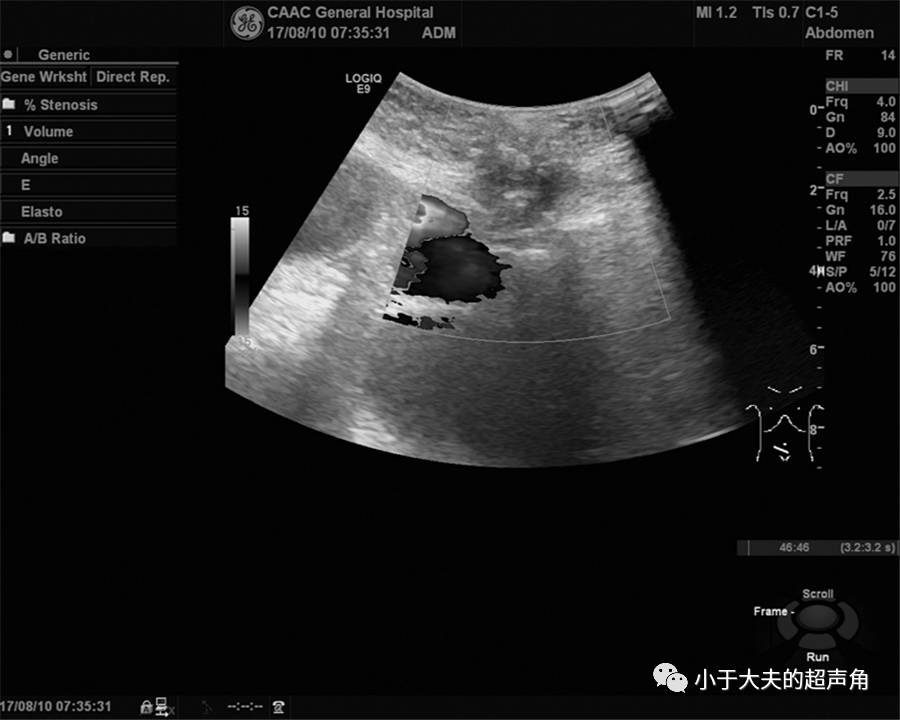

上图:CDFI:偏低回声内未见明显血流信号。

上图:CDFI:内部也未探及明显血流信号。